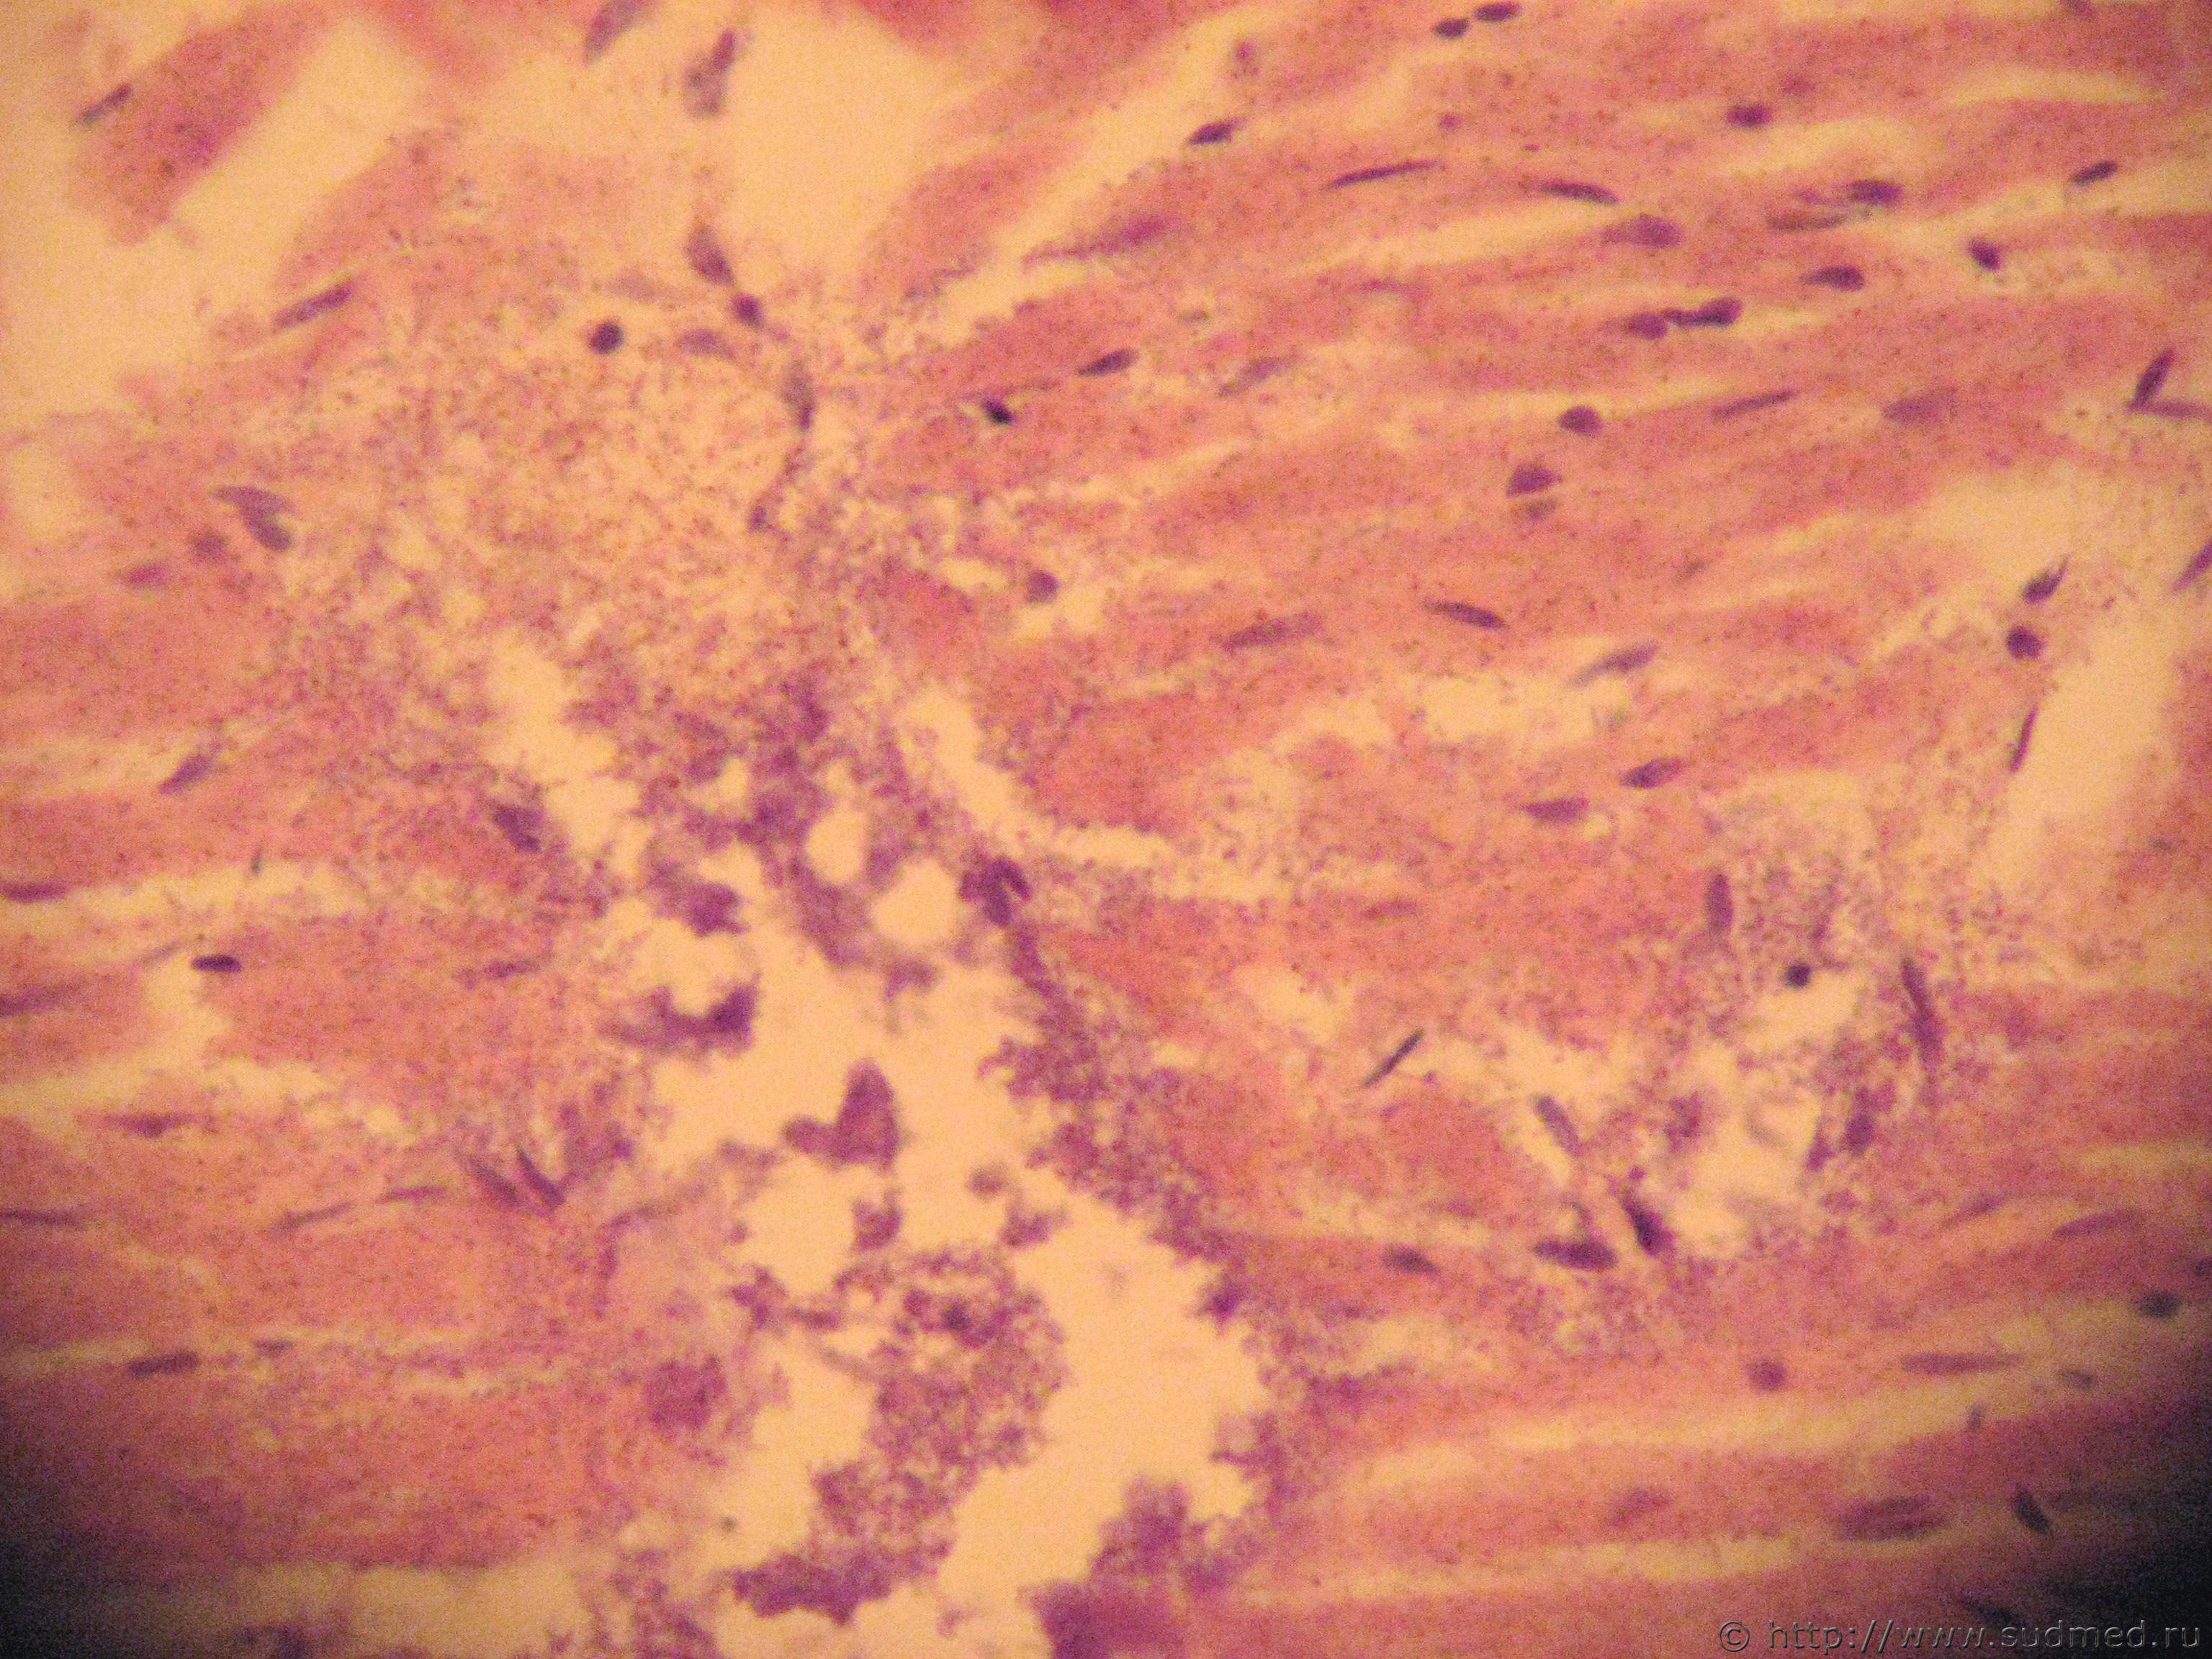

колониии микобактерий в сосудах и периваскулярно:

1. в миокарде, 2. в почке, 3. в околонадпочечниковой клетчатке

Эскизы прикрепленных изображений

Судебная медицина - Прикрепленное изображение Судебная медицина - Прикрепленное изображение Судебная медицина - Прикрепленное изображение